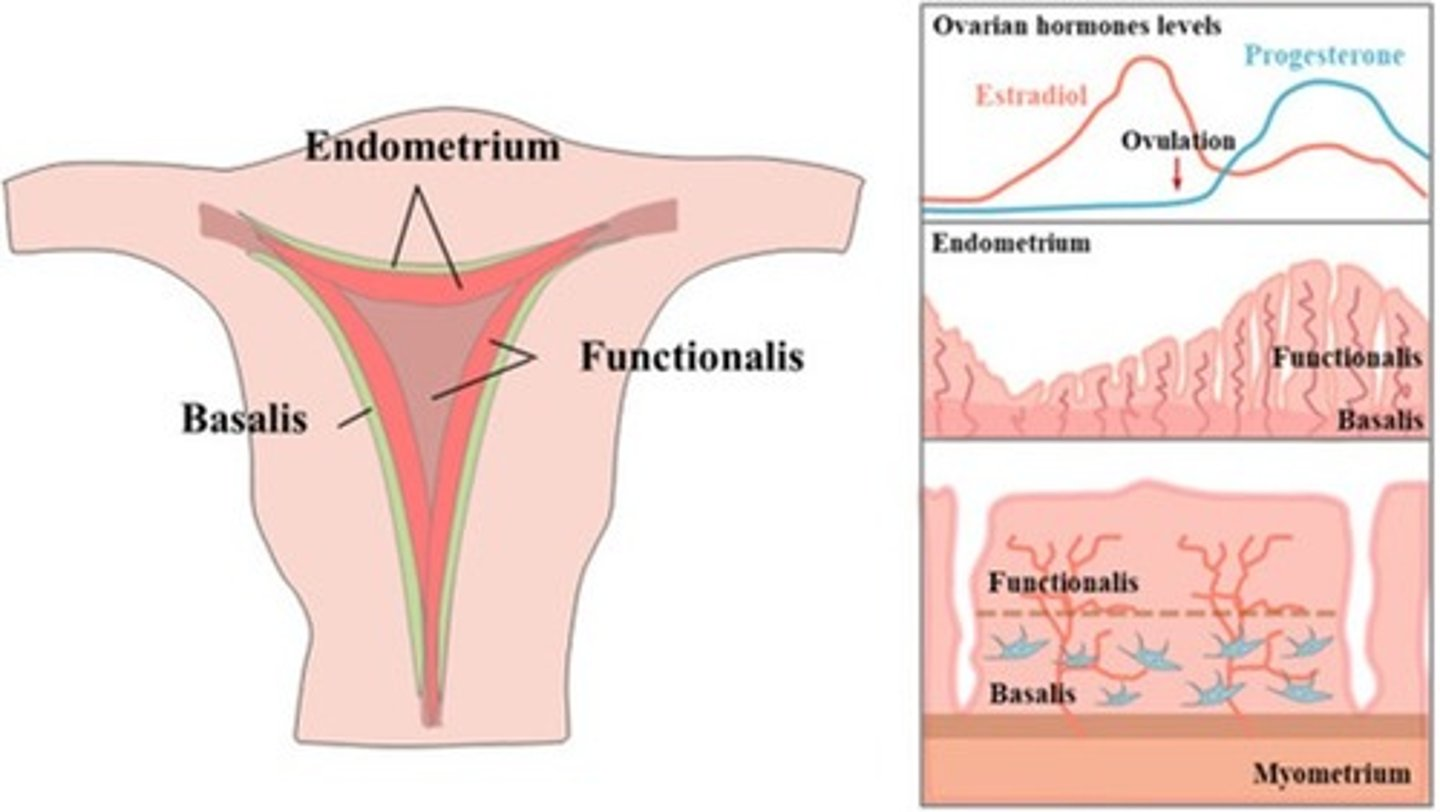

What are the 3 layers of the uterine walls?

inner- endometrium

middle- myometrium

outer- serosa

What are the 2 layers of the endometrium?

1. functionalis

2. basalis

The functionalis layer is a ___ layer that ___

superficial; sheds during menstrual cycle

The basalis layer is a ___ layer that is ___

deep; permanent